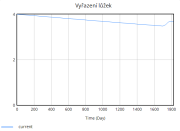

| 22:33, 15 June 2025 | 1 VyřazeníLůžek.png (file) |  |

7 KB | Kozo01 | 1 | |